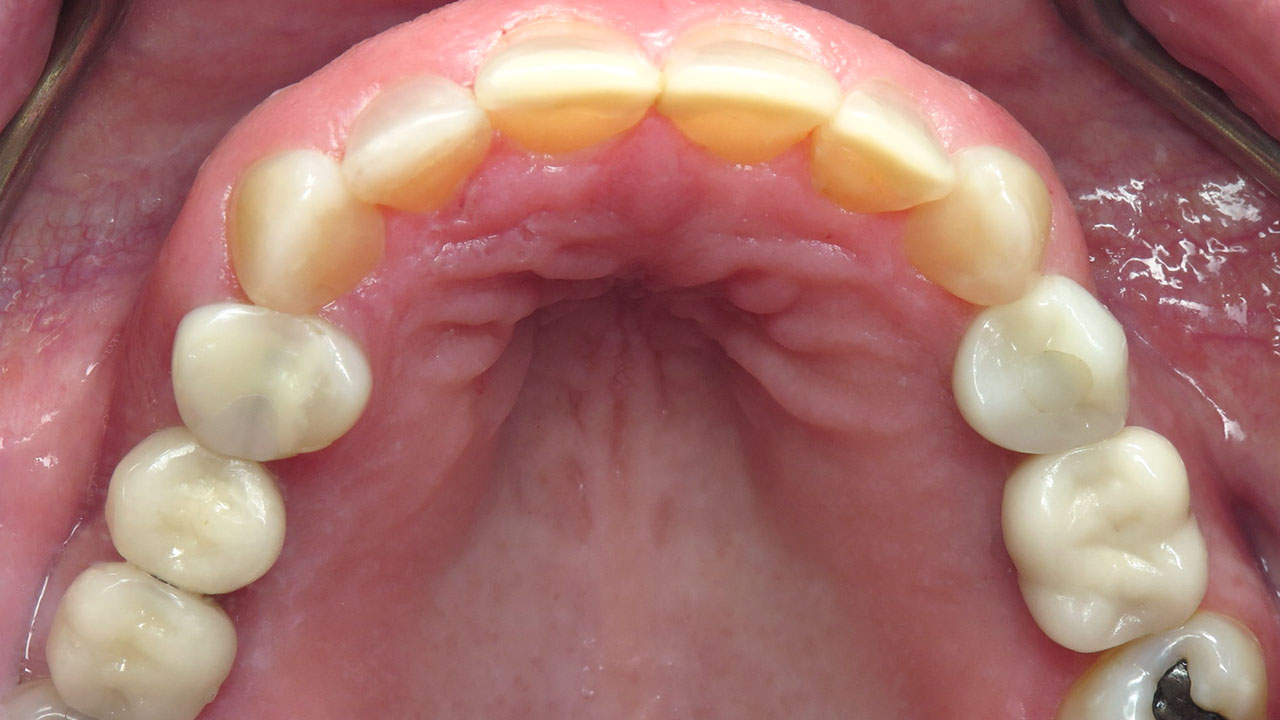

Conservative composite bonding to rebuild and protect the worn edges of the upper and lower front teeth.

Composite bonding on seven upper teeth and eight lower teeth.

The worn edges were rebuilt to protect exposed dentin, improve comfort, and restore a more natural appearance while allowing the patient time to consider more comprehensive treatment options in the future.

Instead, conservative bonding was used to rebuild the worn edges of the upper and lower front teeth. The treatment protected the exposed dentin and improved comfort and appearance while preserving future treatment options.